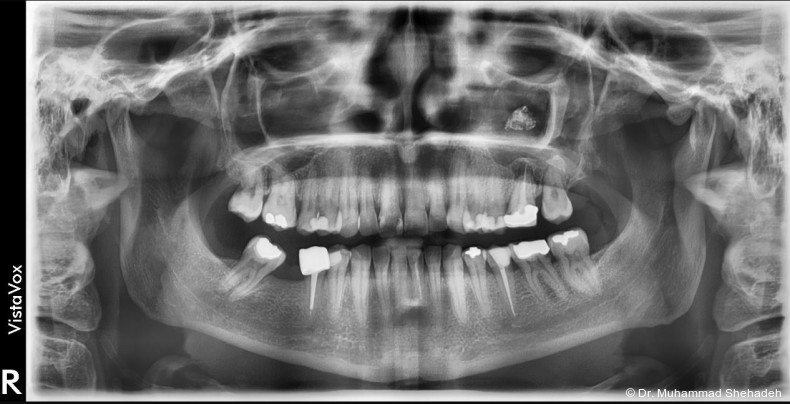

Im orthopantomografischen (OPG) Bild zeigte sich Zahn 26 wurzelbehandelt mit einer periapikalen osteolytischen Läsion. Etwa 15 mm kranial der apikalen Region des Zahns war eine röntgendichte Raumforderung in der linken Kiefer­höhle erkennbar. Die endodontische Versorgung des Zahns 26 erschien insuffizient. Der Zahn war klopfemp­findlich.

Radiologisch zeigte sich die retrograde Füllung im Rahmen der WSR regelrecht. Auffällig war, dass die ­beiden bukkalen Wurzeln nicht gefüllt waren; möglicherweise war die Füllung aufgrund der chronischen Entzündung resorbiert. Dem weiterbehandelnden Zahnarzt wurde daher eine Revision der Wurzel­kanal­behand­lung empfohlen.